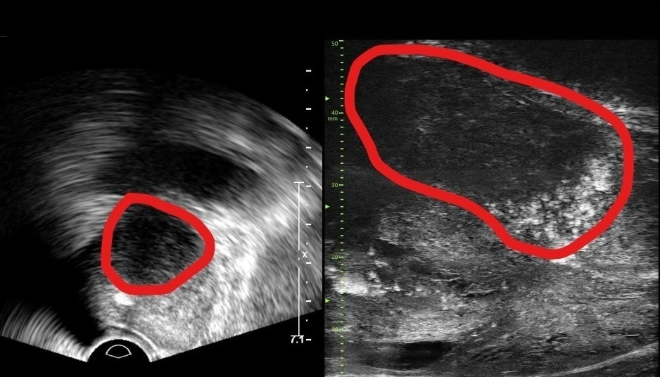

[로이슈 전여송 기자] 분당서울대병원은 본원 비뇨의학과가 기존 초음파보다 3배 더 높은 해상도의 실시간 영상을 통해 전립선 종양 평가가 가능한 마이크로 초음파 장비를 국내 최초로 도입했다고 24일 밝혔다.

29MHz 마이크로 초음파를 사용하는 이 장비는 전립선과 주변의 해부학적 구조를 선명히 표시하고 표적 조직검사를 유도한다. 의심 영역을 실시간으로 확인하면서 전립선 조직의 미세한 변화와 병변을 식별하고 조직검사 채취를 위한 바늘을 정확한 위치에 삽입할 수 있다는 장점이 있다.

또한, 전립선 암 진단을 위한 초음파 검사 가이드인 PRI-MUS(Prostate Risk Identification Using Micro-Ultrasound) 위험도 식별 시스템과 연계돼있어 전립선암 병변의 악성 가능성 평가는 물론, 어느 부분에서 조직을 채취해야 하는지 정확히 판단할 수 있게 한다. PRI-MUS는 초음파 상 병변의 모양이나 크기를 자동으로 판단해 병변의 악성도를 1~5단계(높을수록 위험)로 분류하기 때문에 불필요한 조직검사를 줄이면서도 암을 놓치지 않게 돕는다.

기존의 경직장 초음파는 해상도가 낮아 전립선 종양, 특히 작은 암 병변을 감지하는 데 한계가 있었다. 하지만 마이크로 초음파의 높은 해상도와 실시간 영상의 시각화는 자기공명영상(MRI)으로 발견할 수 없는 전립선암을 찾을 때도 충분히 기여할 것으로 기대하고 있다. MRI 검사 보다 환자의 신체적, 심리적, 경제적 부담도 적을 수밖에 없다.